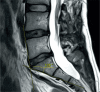

Figure 3

Vertebra dimensions of the middle of the last two lumbar vertebrae corpuses were measured